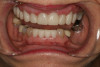

Fig 3. Preoperative condition before functional rehabilitation.

Figure 3